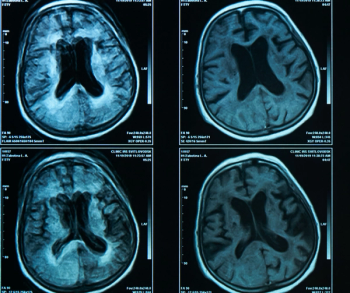

In a recent video interview, Kathy Schilling, M.D., discussed findings from a study of ProFound AI, an adjunctive artificial intelligence (AI) software for digital breast tomosynthesis (DBT), that demonstrated a 23 percent increase in breast cancer detection in comparison to DBT alone.